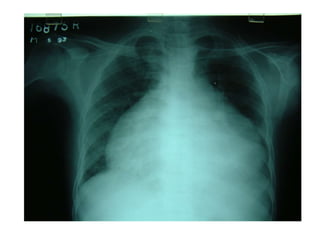

• Pericardial effusion------------

tampnade